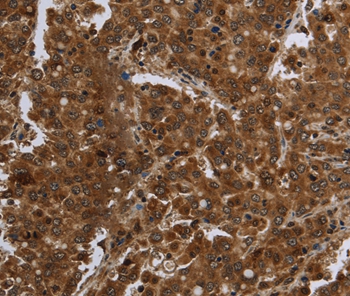

Immunohistochemical analysis of paraffin-embedded Human liver cancer tissue using #36468 at dilution 1/60.

应用详情:Immunohistochemistry: 1:100-1:300